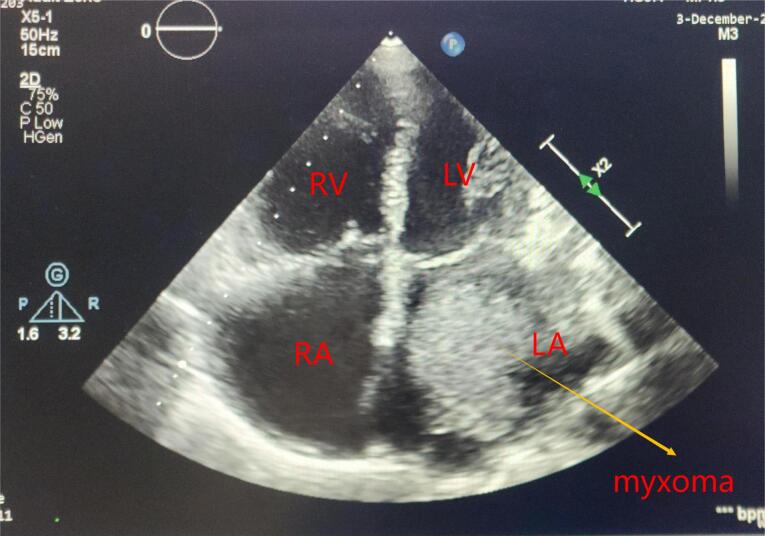

Introduction: Cardiac myxomas are the most common primary cardiac neoplasm (30-50%) with clinical incident of 0.5/ million population. Tranthoracic echocardiography remains the investigation of choice. Surgical excision is curative. The present study aims to analyze demographic and clinical characteristics as well as surgical outcomes in terms of mortality and recurrence of cardiac myxoma.

Methods: Thirty patients of cardiac myxoma who met the inclusion criteria during study period study period, January-2018 to April-2024 were included. Data was analyzed for demographic characteristics, echocardiographic findings of myxoma and associated valve lesion, associated valve surgery and survival outcome.